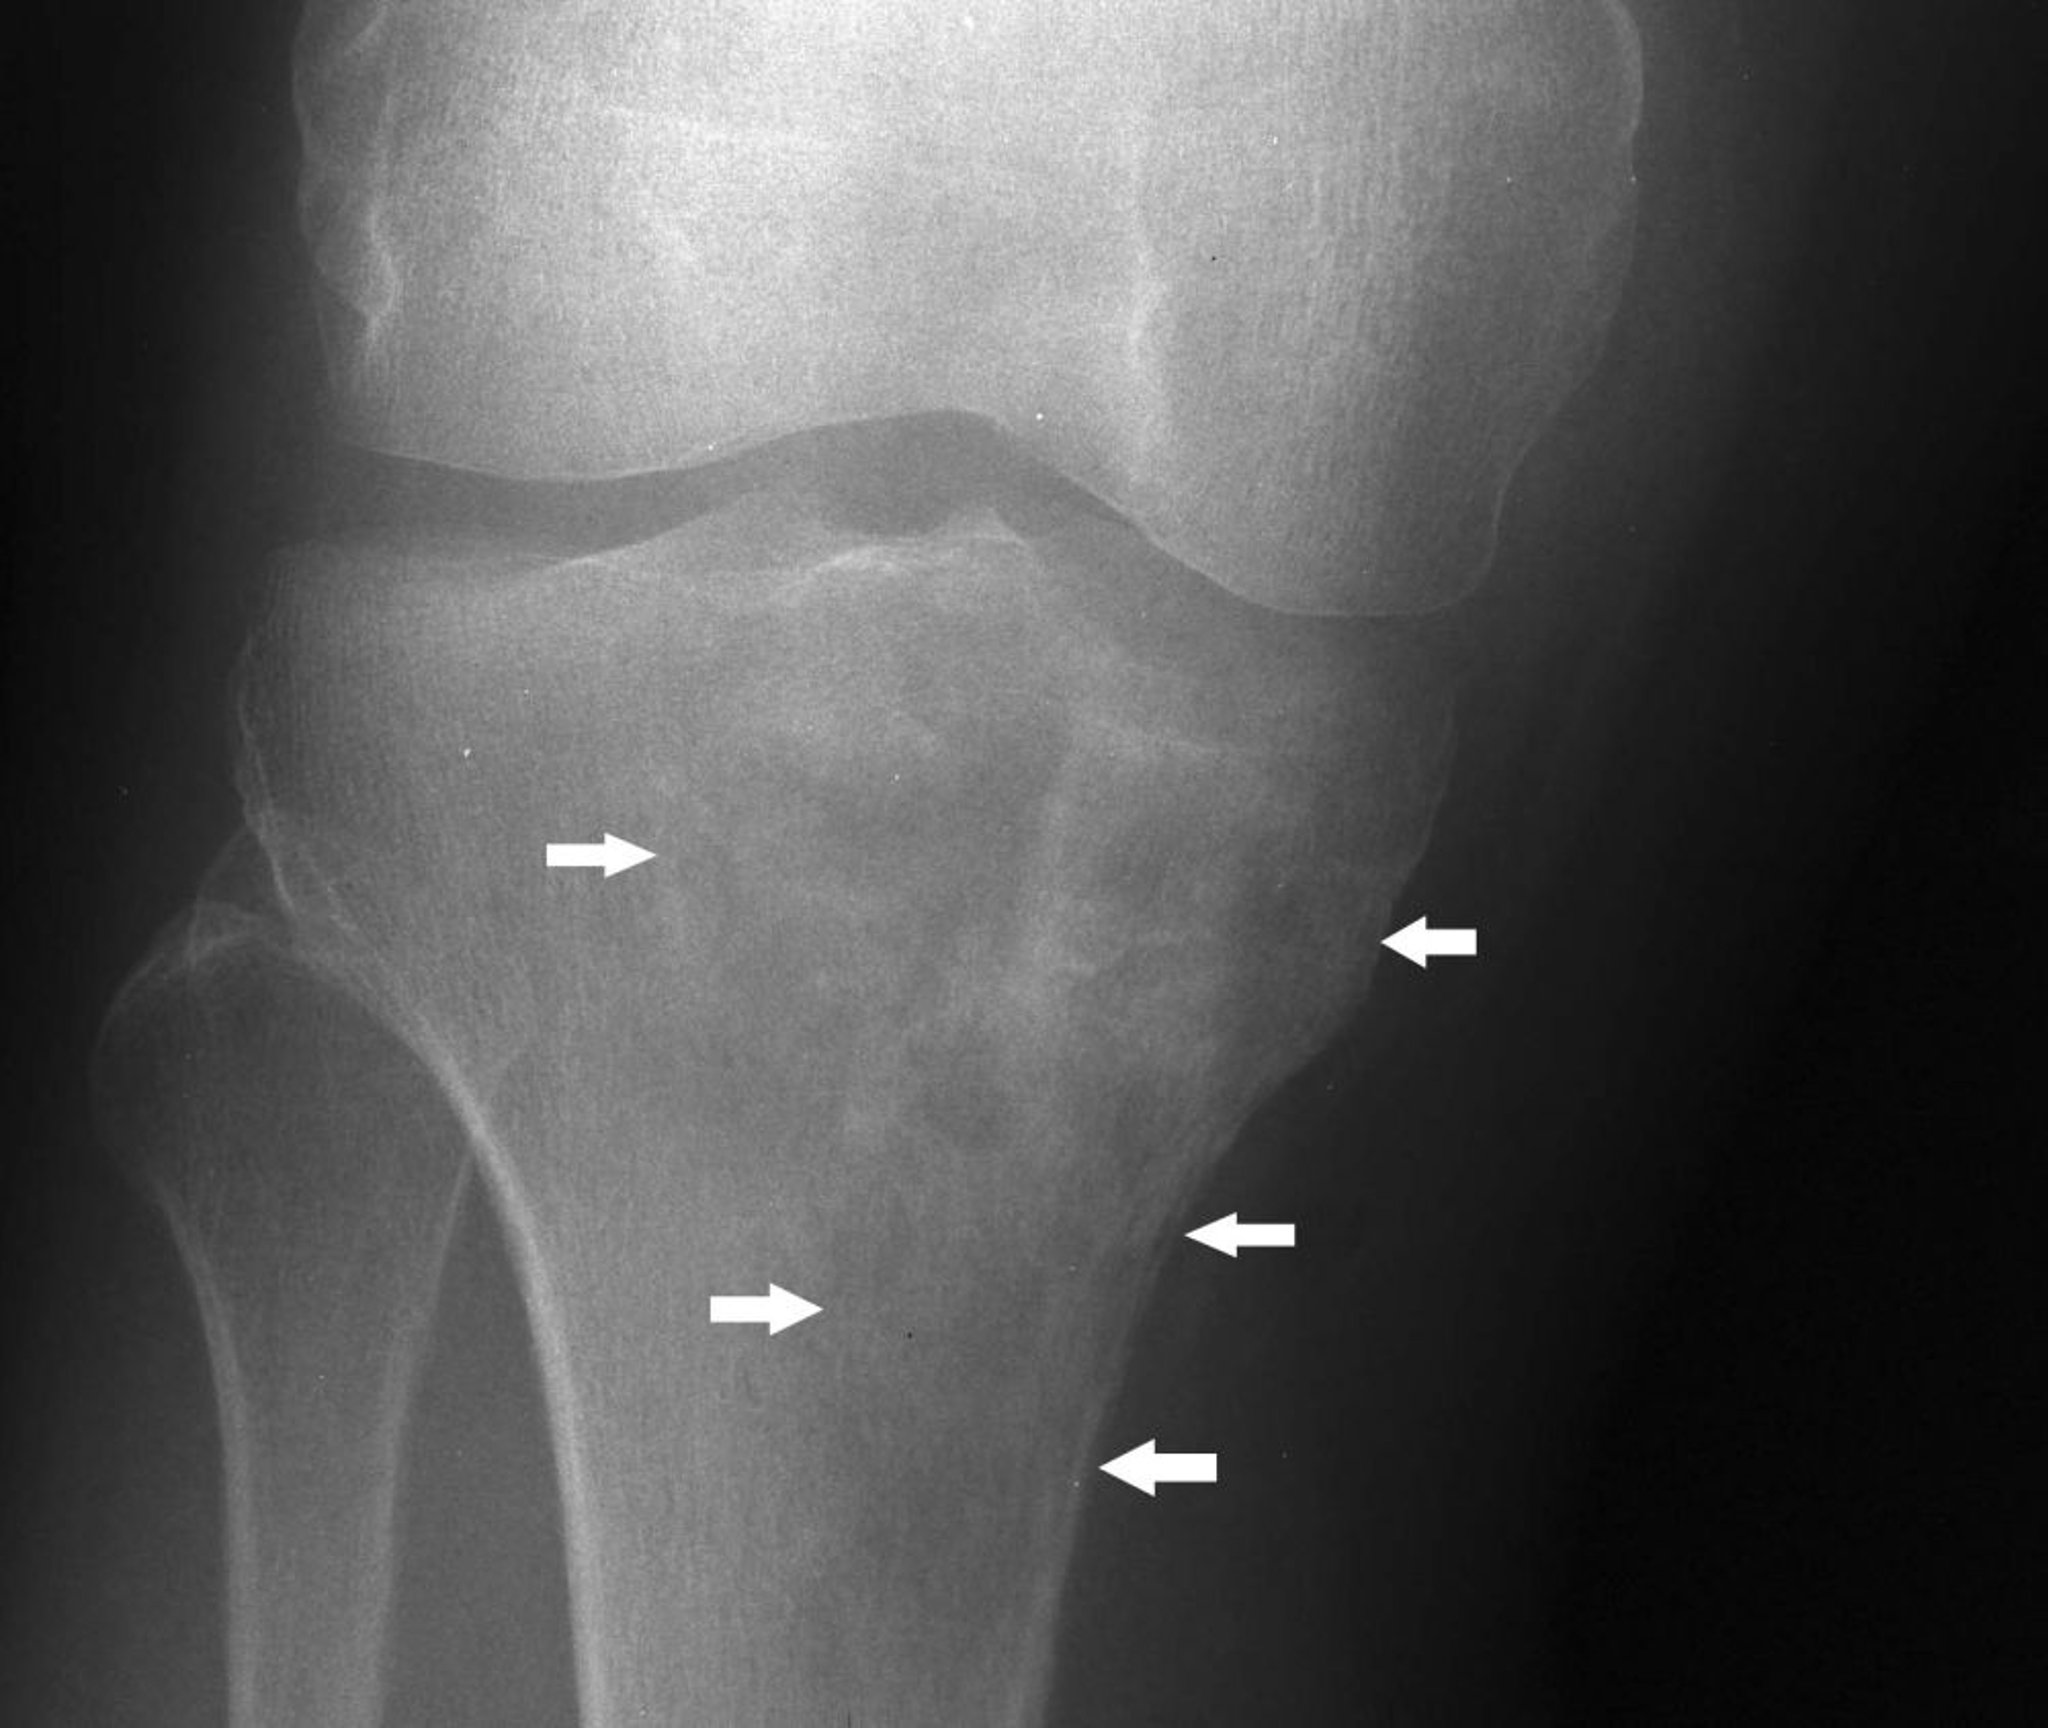

このX線写真では,膝関節下方の脛骨の中に,融解像と硬化像の混在したリンパ腫(矢印)が認められる。

Image courtesy of Michael J.Joyce, MD, and Hakan Ilaslan, MD.